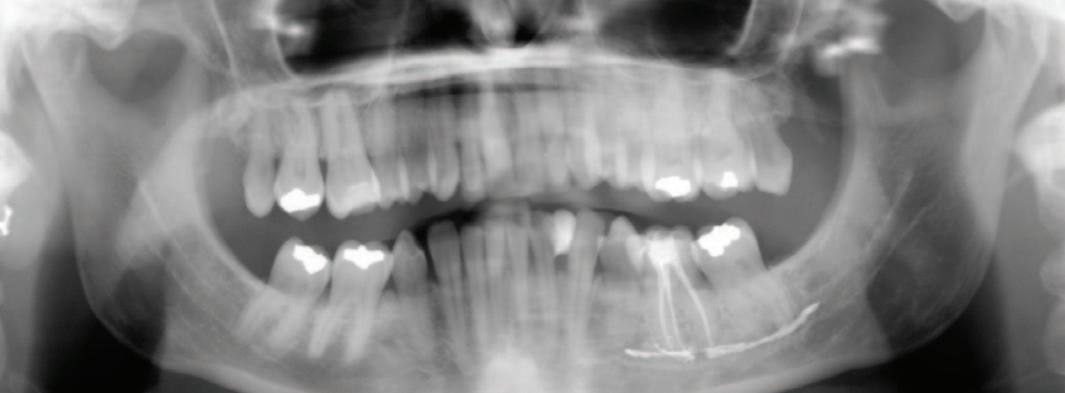

FIGURE 1: Orthopantogram post endodontic treatment demonstrating the extension of the root canal material (AH Plus) along the inferior alveolar canal.

Radiographic examinations consisted of digital orthopantomogram (OPG), peri-apical (PA), and cone beam computed tomography (CBCT) scans. The scans revealed that the lower left first molar root canals were obturated with a radiopaque material, and showed root canal filling extending beyond the apices of the tooth and approximately 5cm along the mandibular canal ( Figures 1 , 2 and 3 ).